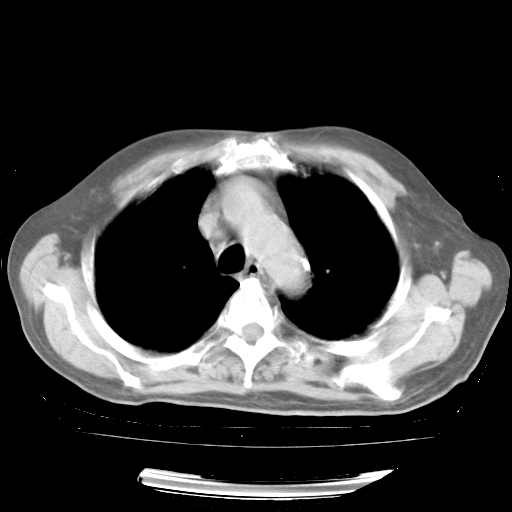

4月28日肺部CT——再次出现类似去年5月9日——透光度降低,“间质性”改变。

4月28日肺部CT——再次出现类似去年5月9日——磨玻璃样、间有“粟粒样”改变。

4月28日肺部CT